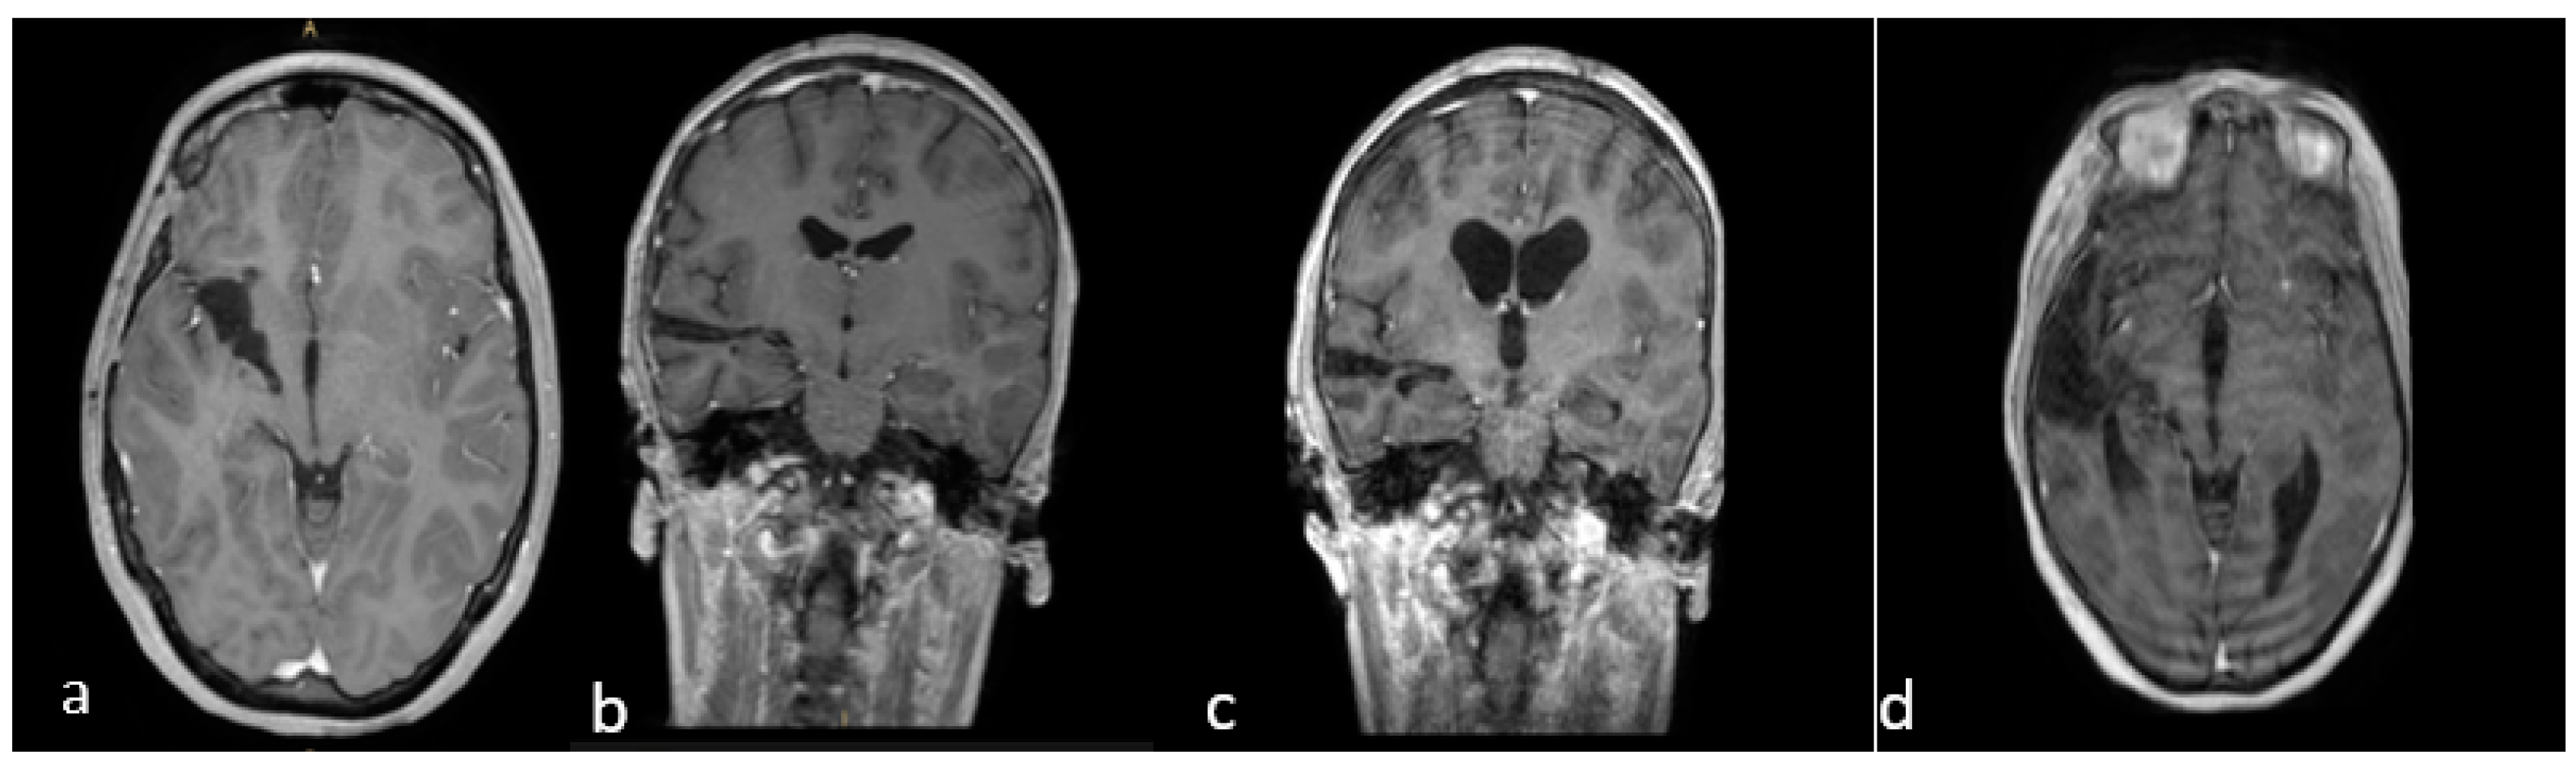

Figure 3.

(a–d) Early postoperative brain MRI with gadolinium. (a,b) An early postoperative brain MRI, T1-weigthed with gadolinium in the axial (to the left) and coronal plane (to the right), for Case A in Figure 2. (c,d) An early post operative MRI, T1-weigthed with gadolinium, for Case B in Figure 1. In detail: In accordance with the nTMS data, we performed a transsylvian approach for Case A (a,b) obtaining a gross total resection (GTR). In Case B (b–d), we performed a trans-temporal approach, obtaining a subtotal resection (STR).